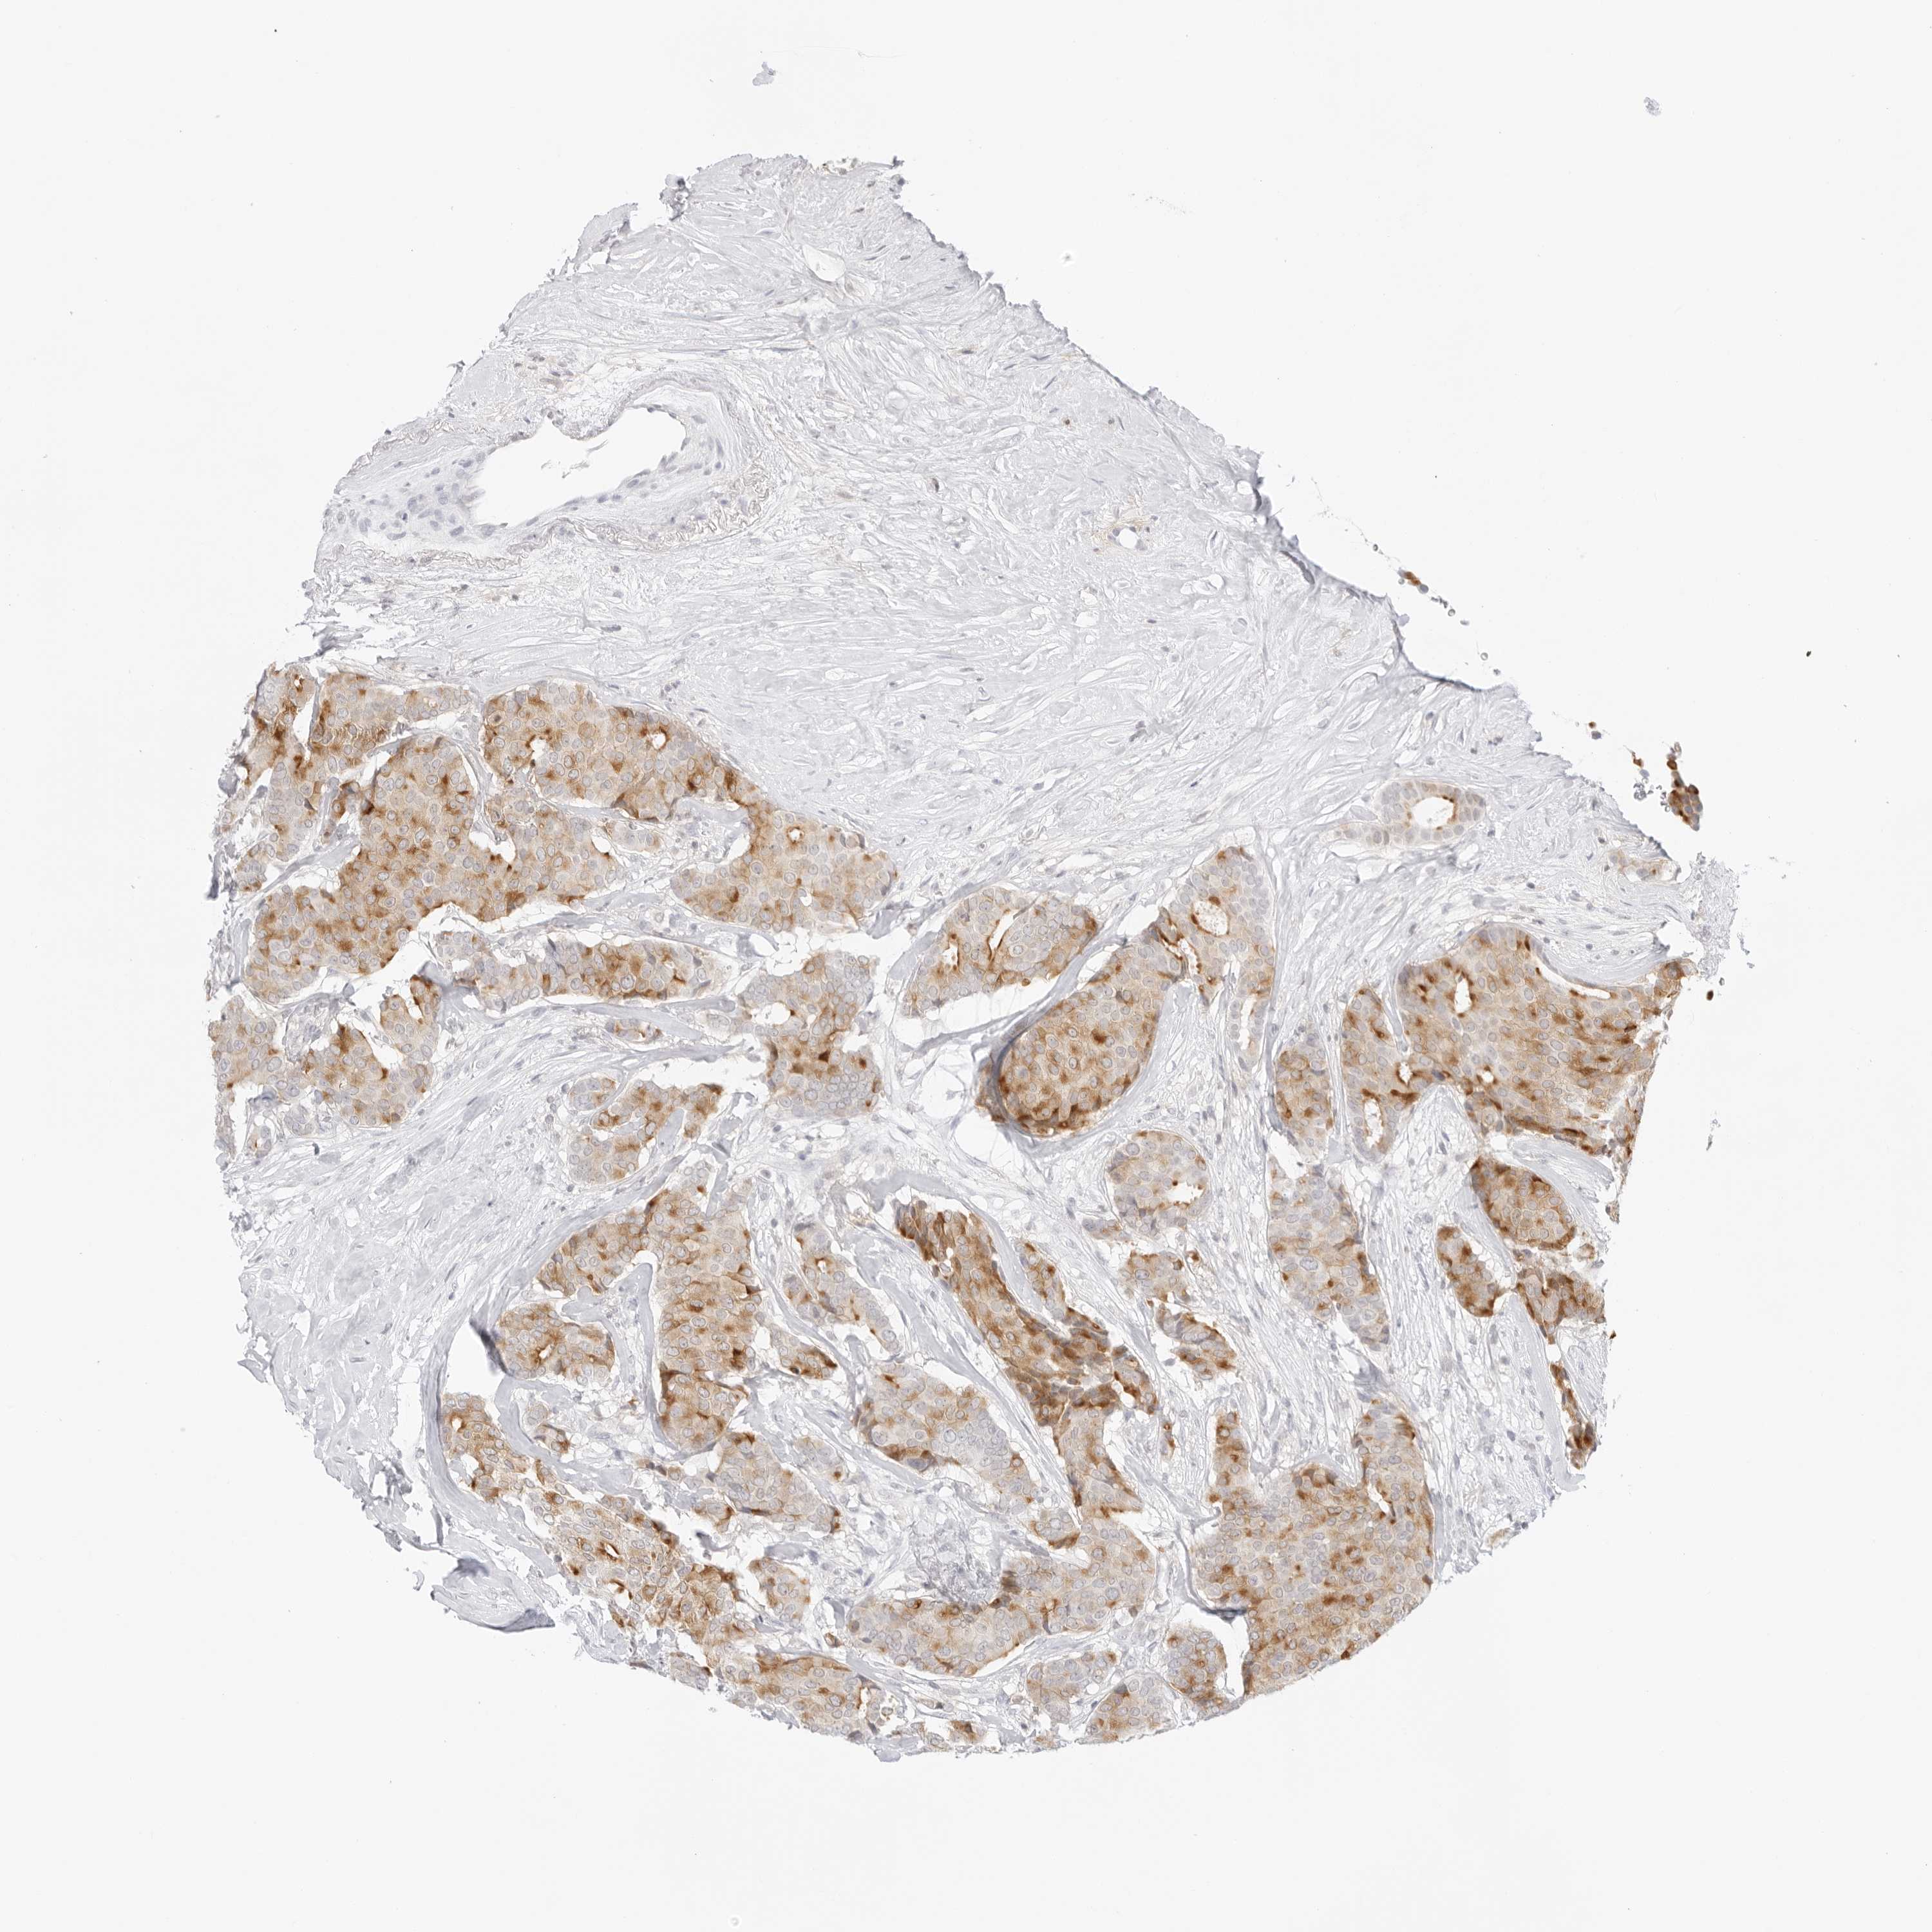

BRCA TCGA BRCA VALIDATION PROTEIN EXPRESSION

ANTIBODIES

AND

VALIDATION